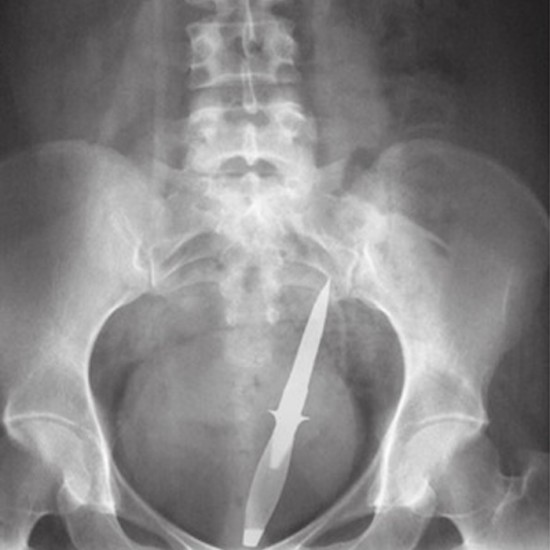

Röntgen filmlerinden "akıl almaz şeyler

Hastane koridorlarına düşenler bilir… Doktora görün, tahlilleri yaptır, röntgenleri çektir falan filan derken sayılmadan ömür gider. Gelin ki bu sefer ilginç şeyler çıkmış ki görün ağzımız açık kaldı…